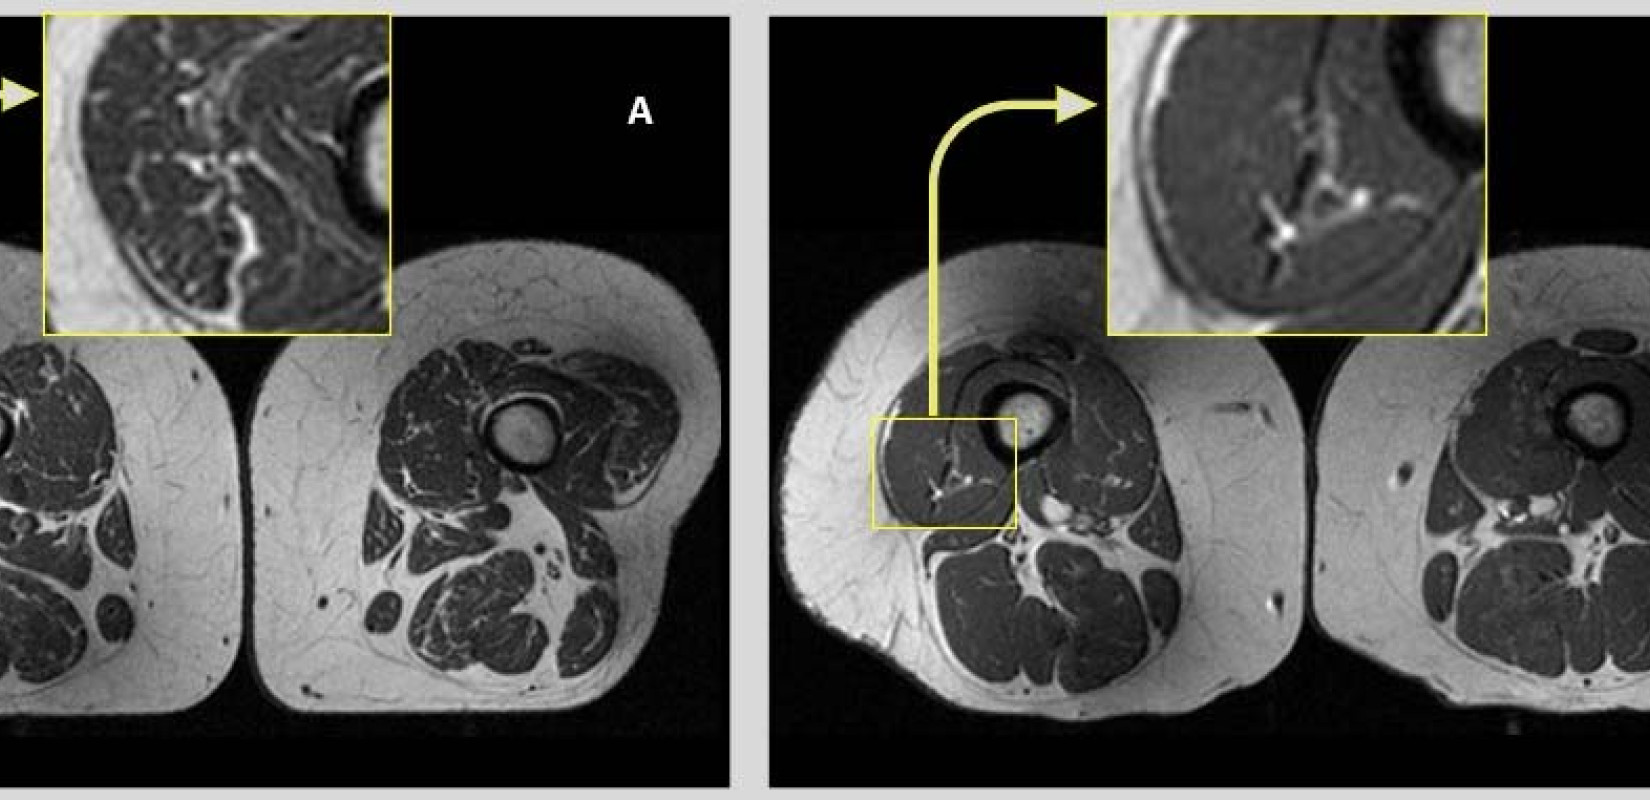

* Επισυνάπτεται φωτογραφία: Εικόνες μαγνητικής τομογραφίας από τις πλευρικές πτυχές των τετρακέφαλων μηριαίων μυών δύο γυναικών που συμμετείχαν στη μελέτη, ηλικίας 58 (Α) και 62 ετών (Β). Στη γυναίκα Α, της οποίας η διατροφή αποτελείτο κατά 68% από υπερεπεξεργασμένες τροφές, οι μηριαίοι μύες παρουσιάζουν πολλές λιπαρές ραβδώσεις. Στη γυναίκα Β, που η διατροφή περιείχε μόνο 36% υπερεπεξεργασμένα τρόφιμα, οι μύες των μηρών παρουσιάζουν λιγότερες λιπαρές ραβδώσεις.